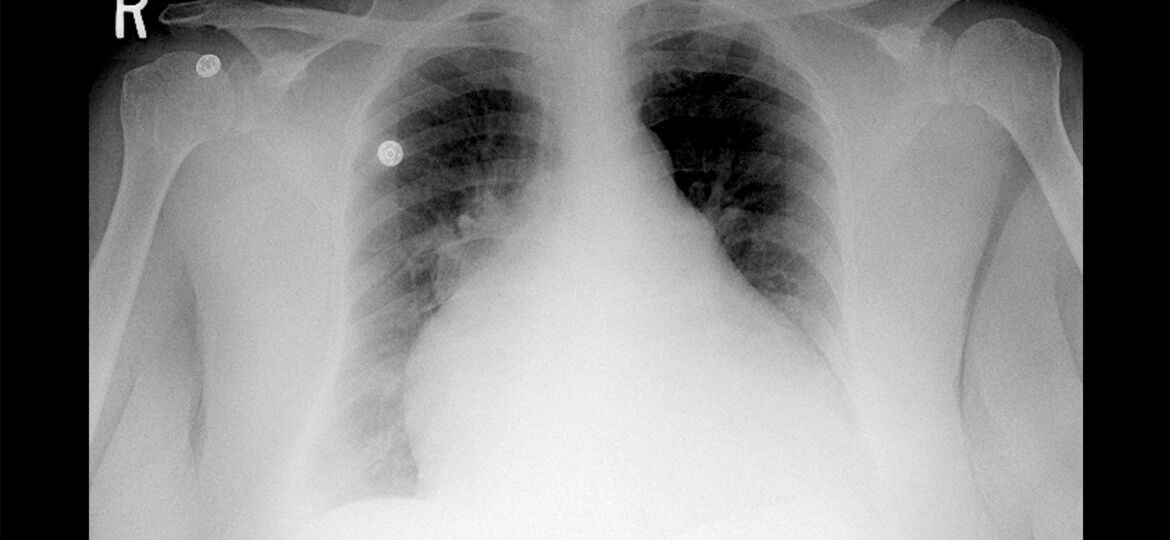

MedPage Today) — Obesity cardiomyopathy (OCM) was identified as a distinct pathology associated with sudden cardiac death (SCD) based on records from a national referral center in the U.K.

Autopsies showed that out of more than 6,400 SCDs, 53…